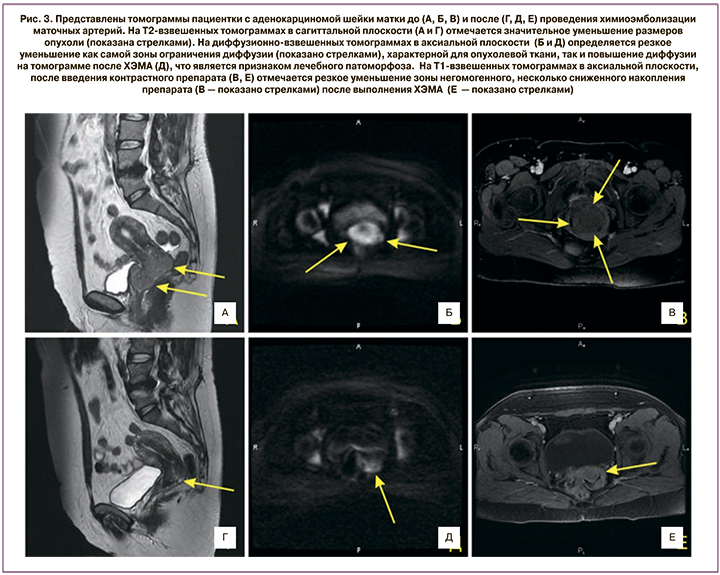

По данным МРТ, после проведения химиотерапии при IB2 и IIA2 стадиях РШМ объем опухоли уменьшался до 24,4 (19,7) см3 (на 33,3%). При IIB стадии заболевания объем новообразования достигал 34,1 (16,5) см3, уменьшаясь на 47,5%. При IIIB стадии данный показатель оказался 34,6 (11,5) см3 (разница с показателем до начала лечения 52,1%; рис. 2–3).